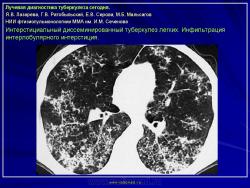

Лучевая диагностика туберкулеза сегодня

Я.В. Лазарева, Г.В. Ратобыльский, Е.В. Серова, М.Б. Мальсагов

НИИ фтизиопульмонологиии ММА им. И.М. Сеченова